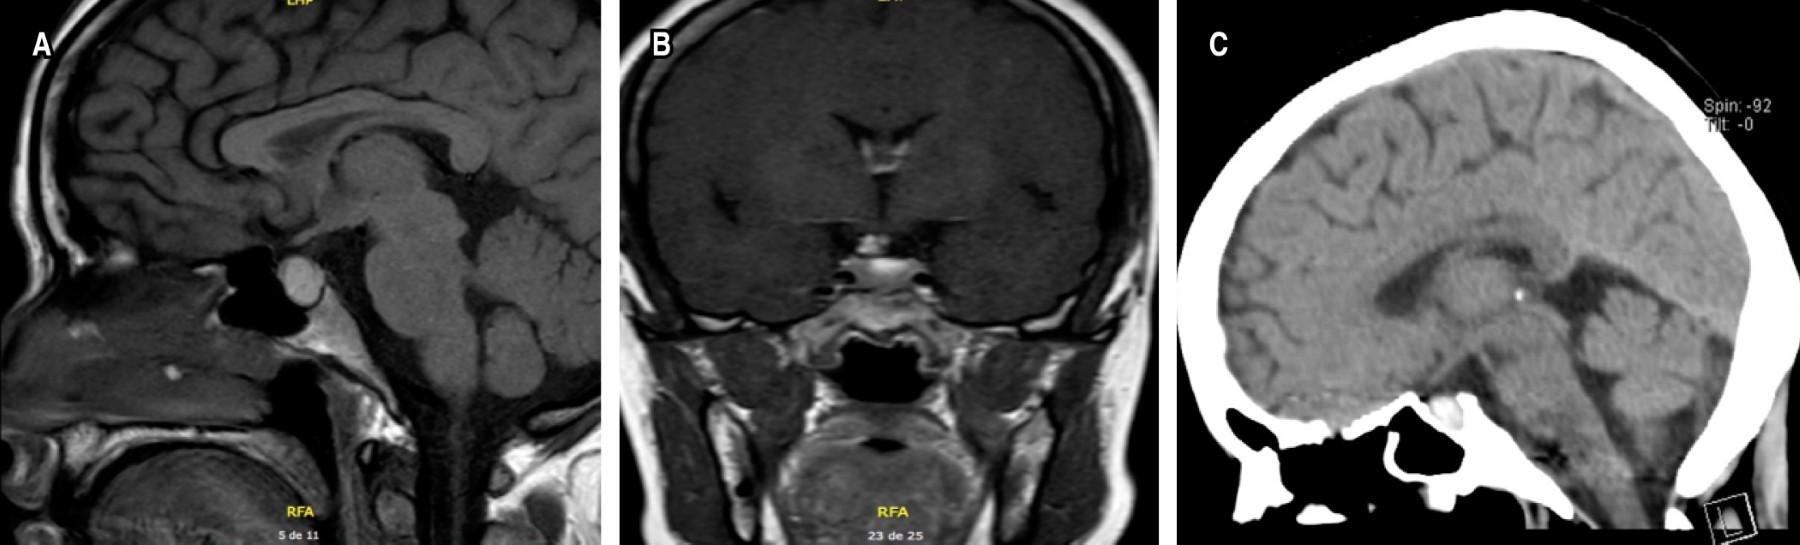

El NIHSS de ingreso fue de 14 puntos, la tomografía de cráneo simple inicial (Figura 2) mostraba un ASPECT 10/10, y una lesión neoplásica hipofisaria 5 × 6 mm sin sangrado intratumoral. La angiotomografía de vasos intracraneales evidenciaba una oclusión distal a la bifurcación de la arteria cerebral media (ACM) izquierda porción M3 (Figura 3). La glucometría de ingreso y sus signos vitales estaban dentro de límites normales.

Figura 2